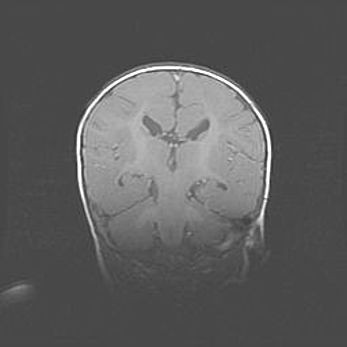

Церебральная ишемия II.

Возраст: 5 дней

Вес: 3400 г

Пол: женский

Окружность головы: 35 см

Срок гестации: 39 недель

Церебральная ишемия – это заболевание, характеризующееся недостаточностью (гипоксией) либо полным прекращением (аноксией) снабжения мозга кислородом по причине закупорки одного или нескольких сосудов. Это приводит к  что метаболическим расстройствам различной степени тяжести в тканях головного мозга, развитию коагуляционных некрозов и гибели нейронов.